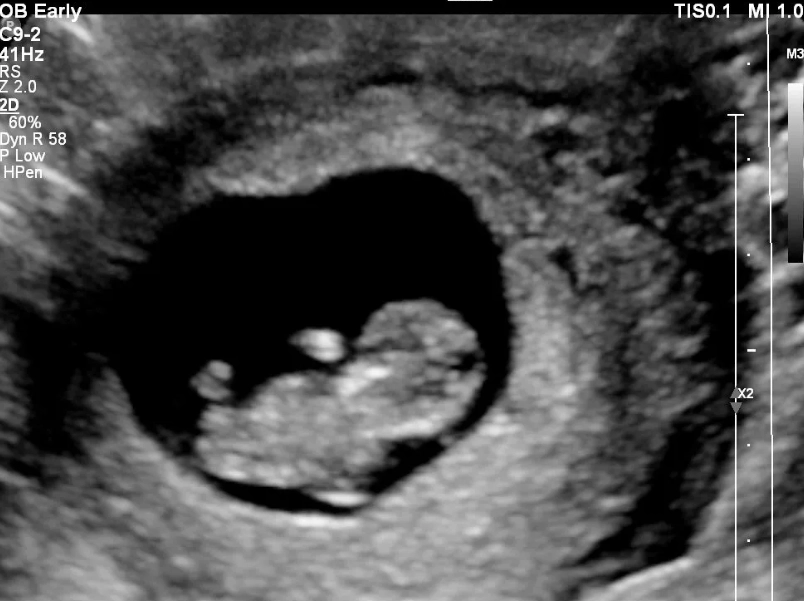

You might have had an earlier scan around 6-8 weeks, maybe to confirm the pregnancy or check the heartbeat. That one's important, sure, but it's often just a little blob and a flicker. The 12 weeks pregnant ultrasound is different. It's the first major, detailed check-up for your baby. Think of it as the end of the first trimester graduation exam.

Sometimes, if your uterus is tilted backwards (a retroverted uterus) or if you have a higher BMI, getting a clear abdominal view at 12 weeks can be tricky. In that case, they might suggest a transvaginal scan. This uses a slender, clean probe inserted into the vagina. It sounds worse than it is – it gets much closer to the uterus and often provides crystal-clear images without the need for a full bladder. They'll talk you through it and always use a fresh cover on the probe.

They'll point things out as they go: "There's the head," "See the heartbeat flickering," "Those are the little arm buds moving." You'll likely see your baby bouncing, stretching, or even sucking its thumb. It's utterly mesmerizing.